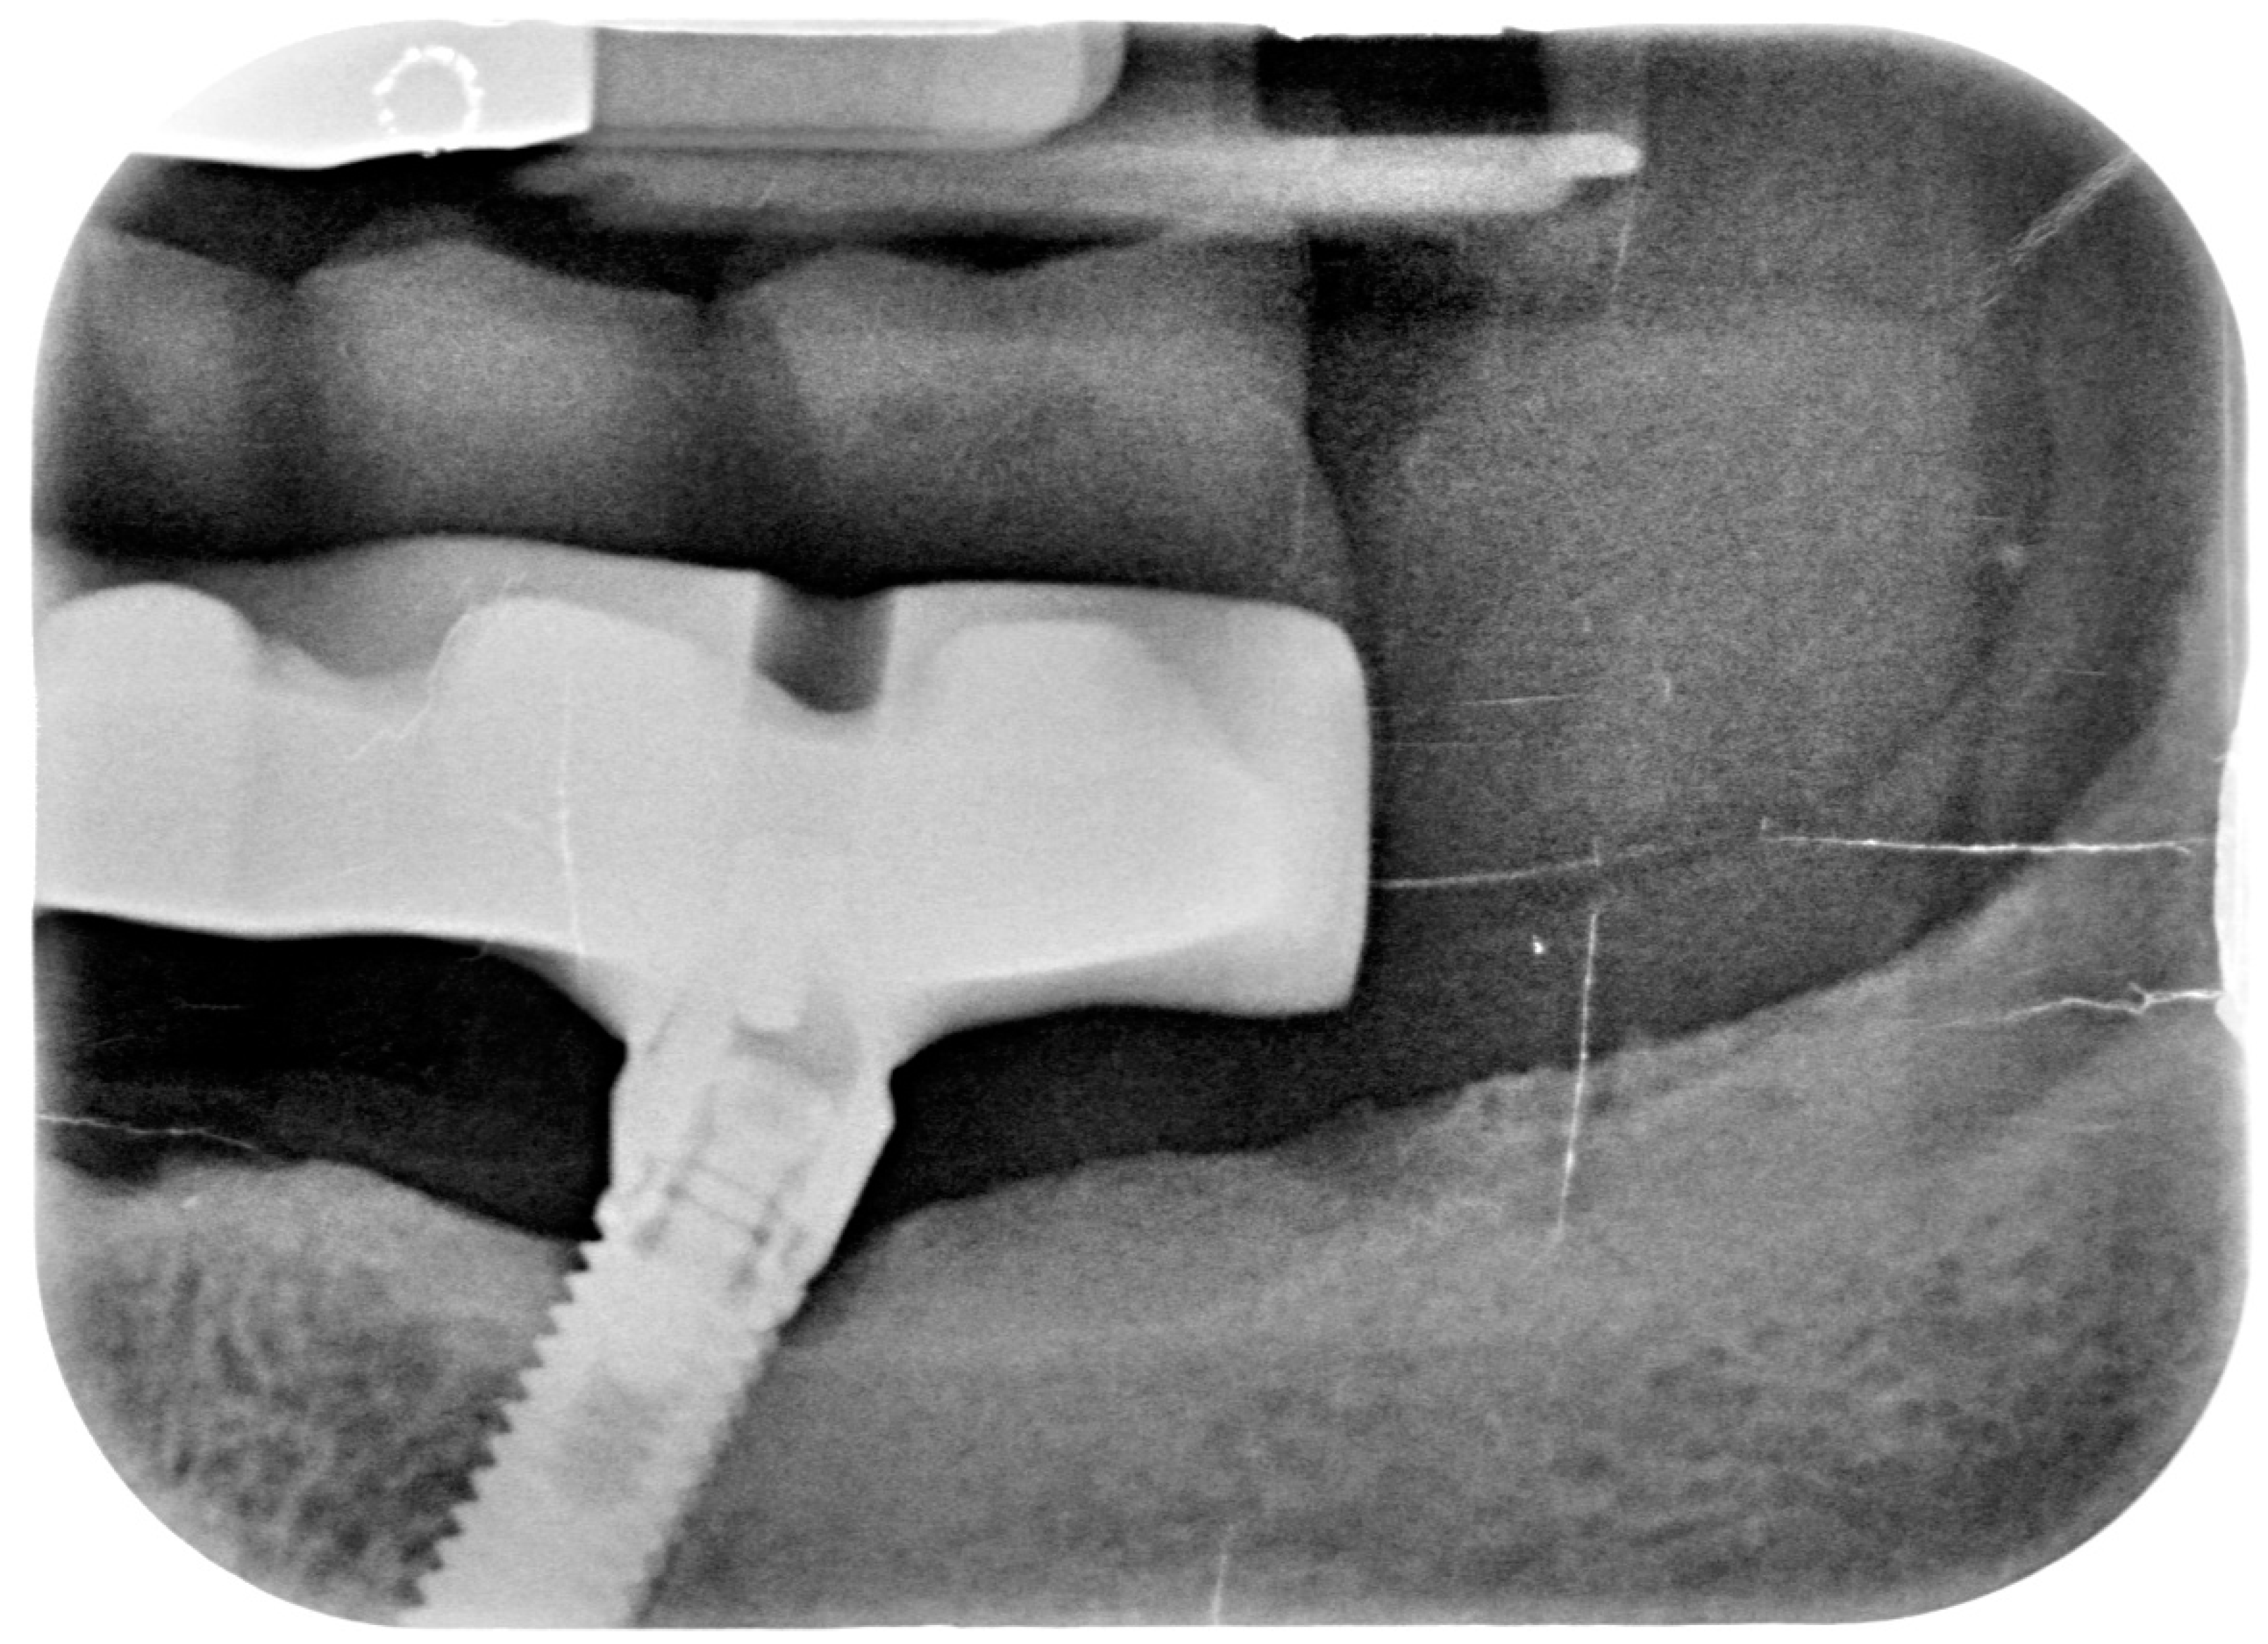

2.2. Case Report 2

2.3. Case Report 3